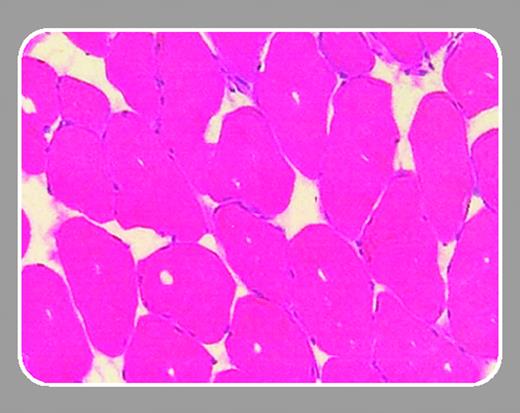

Arruda and colleagues (page 85) report an extension to their previous assessment of adeno-associated virus (AAV)–mediated factor IX delivery to skeletal muscle. In this study, the authors have evaluated the relative efficacy and safety of factor IX expression derived from 3 different AAV serotypes, the most frequently used AAV-2, and AAV-1 and AAV-6. Their investigations, in mice and dogs, show that the expression of factor IX is 10- to 50-fold higher following AAV-1 delivery compared with similar doses of an AAV-2 vector. This finding confirms earlier reports of enhanced transgene expression with intramuscular delivery by AAV-1, although the extent of this enhancement has varied considerably.4 Interestingly, the improvement in factor IX expression is only partially explained by the 2- to 3-fold increased transduction efficiency with the AAV-1 vector, and thus, other yet-to-be characterized mechanisms provide the biosynthetic advantage seen with this AAV serotype.